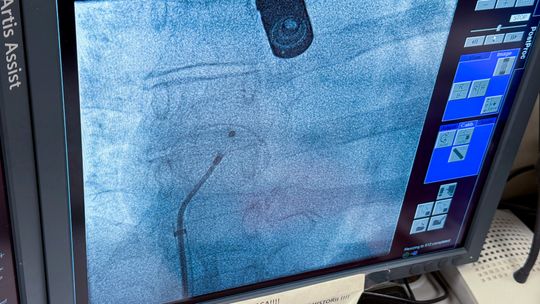

Historyczny zabieg w garwolińskim szpitalu. Po raz pierwszy zamknięto ASD bez operacji

Zdjęcie:

Autor: SP ZOZ Garwolin